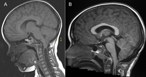

Holocord syrinx presenting with foot drop

Duncan Henderson and others

Journal of Surgical Case Reports, Volume 2019, Issue 4, April 2019, rjz082, https://doi.org/10.1093/jscr/rjz082